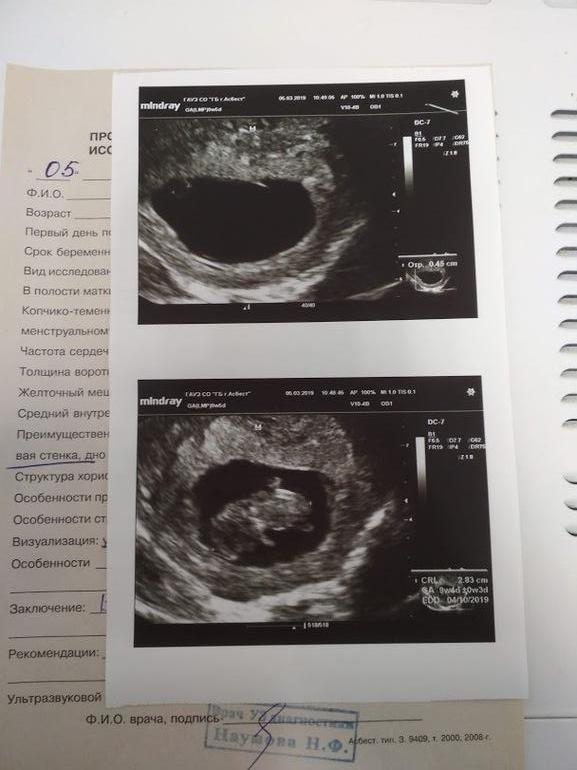

Последние месячные 27.12. Итого имеем 11-ю акушерскую неделю.

Через неделю 27 февраля на моем участке все повторилось. Осмотр,маловата,витамины. Только мой доктор гораздо общительнее оказалась))). Отправила еще через неделю на УЗИ для уточнения срока. Не могла дождаться. А то вроде как бы да, но как бы да неуверенное. Да и срок не ясен совсем. УЗИ отличное. Сердечко бьется. Прикрепились мы справа сбоку. Все по сроку. Ростик 2.83 см. ЧСС 159 и 2 срока 9+4 и 10+3. Второй как я понимаю акушерский. Успокоилась и пошла привыкать к своему новому статусу)))